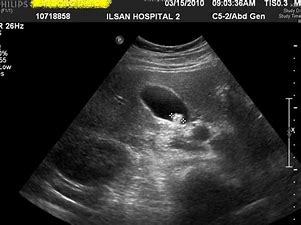

복부 초음파 검사로 진단 ,때론 조영술, CT도 필요

담석 진단을 위한 일차적 검사는 복부 초음파 검사입니다.

초음파 검사는 검사 시간이 빠르며 비침습적인 검사이고 담낭뿐 아니라 담관, 간, 췌장 등의 기관을 동시에 살펴볼 수 있는 장점이 있습니다.

또한 방사선 노출이 없고 황달이나 임신 여부에 지장이 없으며, 아주 작은 담석도 찾을 수 있지만 이는 시술자 능력에 따라 차이가 있을 수 있습니다.